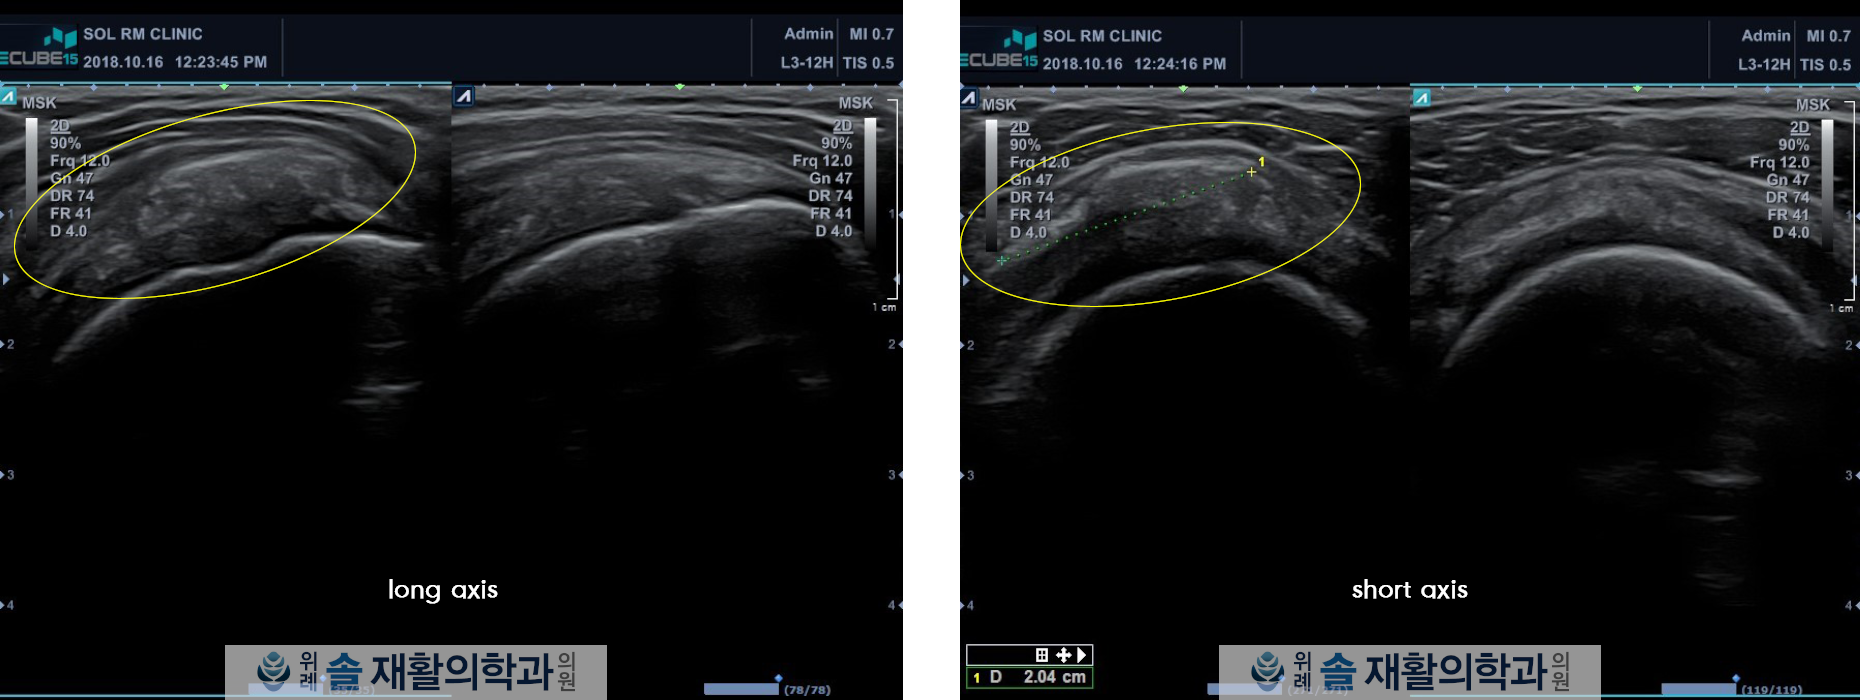

초음파 검사상 우측 회전근대 극상근의 부분 파열이 확인되었으며, 좌측 회전근개 극상근에는 석회성 병변이 발견되었습니다.

치료 종결 후 확인한 초음파에서는 좌측 극상근에 보였던 석회성 병변이 완정히 사라진 소견이 학인되었고, 우측 극상근의 부분파열은 많이 줄어든 모습이 관찰되었습니다.